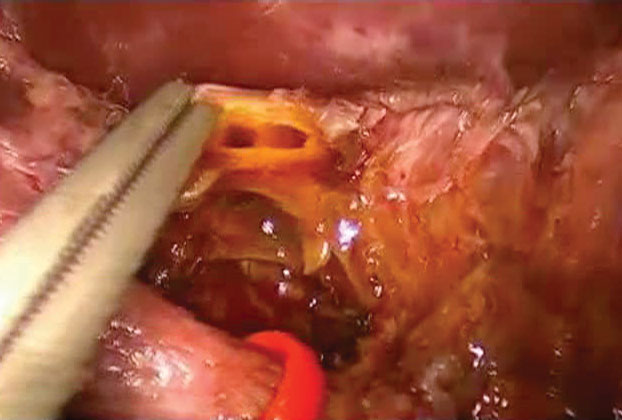

COMMON BILE DUCT DISSECTION AND CYST EXCISION

Dissection begins in the right upper quadrant. Often, the patient has either had a prior cholecystectomy or has had inflammation related to the choledochal cyst, making identification and isolation of the common bile duct difficult. Careful dissection of the structures in the hepatic hilum allows the surgeon to separate the duct from the medially located artery and the posterior portal vein. The duct is then followed into the head of the pancreas to allow for complete distal division. Once divided distally, the duct is freed, allowing its gradual dissection from the neighboring structures of the hepatoduodenal ligament while retracting it superiorly, anteriorly, and to the sides. This allows for dissection under direct visualization, particularly on the posterior plane of the duct. Proximal division is similarly performed above the involved portion of the duct. If necessary, and for the most part in the presence of a large cyst, the cyst can be opened anteriorly prior to its proximal division to clearly assess the needed extent of dissection and to choose the site for proximal division.

A complete excision of the cyst is usually advised, but some authors advocate leaving a 1 mm rim of the cyst wall proximally when a wide anastomosis is not feasible if complete cyst excision is performed.

Figure 4: The distal common bile duct has been divided below the lower end of the cyst.

Figure 5: Proximally, the division of the hepatic duct was performed at the bifurcation to assure a complete excision of the cyst. The bifurcation into the right and left duct is shown.